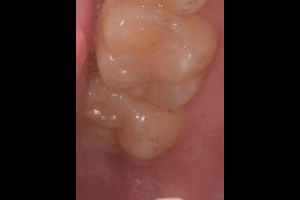

口腔内

- Before

- After

半埋伏の親知らずでした。3糸縫合しました。